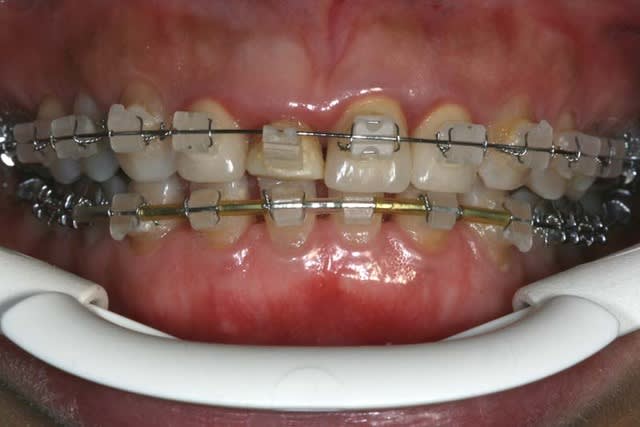

entre temps il y a de l'odf pr réaligner les incisives du bas(diastèmes se modifient d'après la patiente), à la demande de la patiente et parceque la fracture de 11 au bout de tant d'années me questionne...

la CCM est en prov de luxe

(ça tombait bien,la teinte est moyenne,bien qu'elle passe mieux en bouche que sur la photo:le flash?)

la patiente part en vacances

je la referai en septembre

avec ou sans chir?...

il y a eu remodelage naturel(comme quoi entre la theorie et la clinique): peut on le considérer comme suffisant?

autre question:"les incisives du bas"

la patiente a entamé son traitement odf pr une demande esthetique(marre des diastème)

pr des raisons fonctionnelles aussi,cela ns paraissait une bonne idée

elle a une microdontie relative de ces insicives qui st maintenant redressées, alignées avec des diastèmes equidistants

et maintenant....

que feriez vous?

on comprend mieux la microdontie relative

les diastemes te genent? tu as peur de la recidive apres l'ortho?